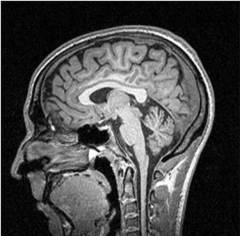

Магнитно-резонансная томография (МРТ)

Исследование основано на взаимодействии магнитного поля и атомов водорода. Процедура длится около 40 минут, стоимость 4-5 тыс. рублей. Этот метод считается точным, так как кости черепа не являются преградой для магнитного поля.

МРТ позволяет выявить:

- опухоли головного мозга;

- признаки инфаркта мозга;

- аномальное развитие сосудов;

- воспаление оболочек мозга.

Результаты помогают врачу определить причину заболевания для эффективного лечения неврита.